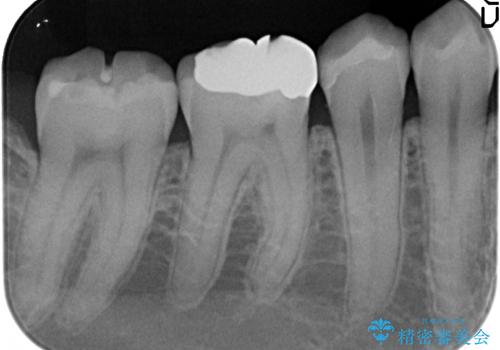

- 右下5番目の歯がしみるので診て欲しいといらっしゃった方の症例です。

虫歯を除去後、セラミックインレーによる修復を行いました。

当院のセラミックインレーはemaxという強度と審美性に優れた材料を使用しています。

またプレス方式でインレーを製作しているため、削り出しで製作するCADCAMより優れた適合性も持ち合わせており、虫歯が再発しにくい修復物です。